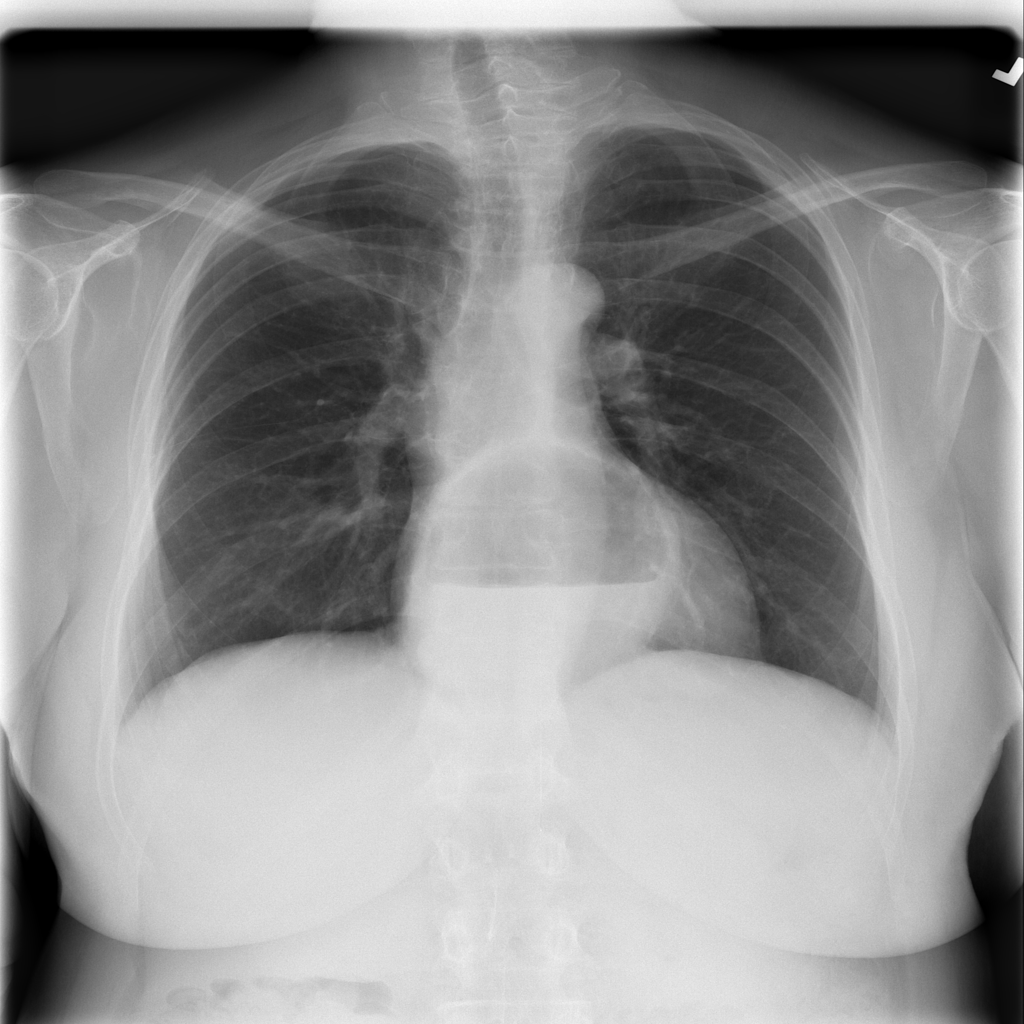

PAT-0ABD · IMG-000Hernia

PAT-0ABD · IMG-000

PA